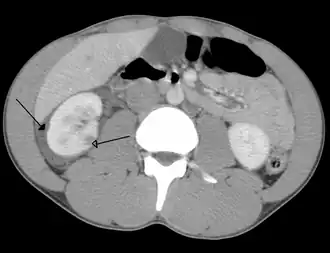

| Trauma abdominal resultando em uma contusão no rim direito (seta aberta) e sangue ao redor do rim (seta fechada), conforme visto em tomografia computadorizada. | |